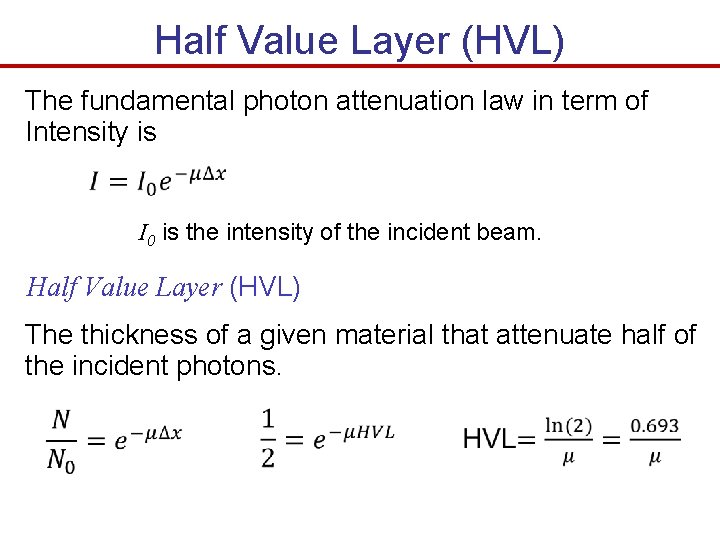

Half Value Layer (HVL) The fundamental photon attenuation law in term of Intensity is I 0 is the intensity of the incident beam. Half Value Layer (HVL) The thickness of a given material that attenuate half of the incident photons.